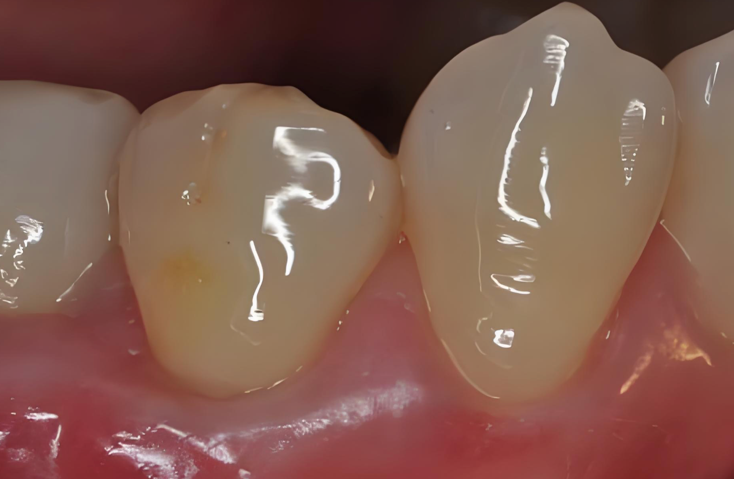

食物残渣和细菌在此地长期“安居乐业”,形成菌斑生物膜。它们产酸腐蚀牙面,从而引发邻面龋。这种蛀牙极具隐蔽性和欺骗性:从牙齿的正面看过去,可能仅仅是一条细微的黑线甚至完全看不见,但在X光片下,它可能已经在牙齿内部蛀成了一个巨大的“隧道”或“山洞”。等到出现疼痛症状时,蛀洞往往已经深及牙髓,需要进行复杂的根管治疗了。

图片41.png

图1: X光片示,左数第二颗牙(右上第一磨牙近中)的表面看似只有微小缺损,但其内部邻面已形成大面积龋坏洞,几乎穿透至牙髓。这就是邻面龋的典型特征——“口小底大”。